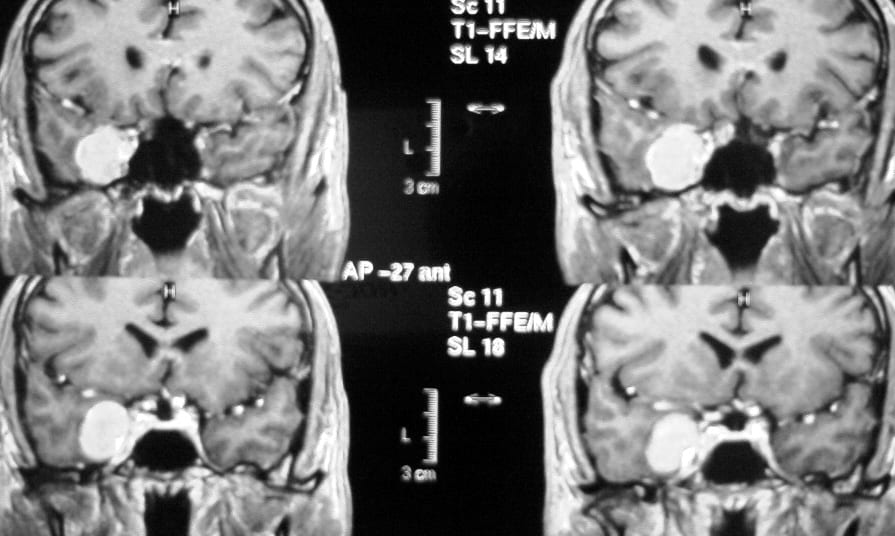

El diagnóstico se puede confirmar y el tumor localizar mediante:

• RM cerebral